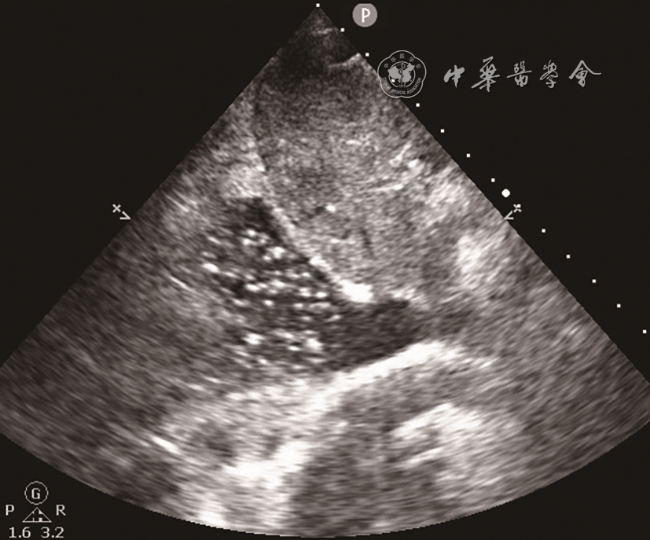

入急诊科时患者血压为60/29 mmHg(1 mmHg=0.133 kPa),心率为143次/min,末梢氧饱和度低,气管插管呼吸机辅助通气。11月26日急诊床旁超声检查提示:肝内多发高回声包块并肝静脉内气体样强回声漂动入下腔静脉、右心,肺动脉内可见大量气体样强回声,考虑产气型肝脓肿破裂(图12动态图1)。急诊平扫CT检查提示:肝多发类圆形混杂气体密度灶,肝内外胆管扩张、积气(图3)。当日血培养检出高黏性肺炎克雷伯菌(Klebsiella pneumoniae,KP),菌拉丝阳性,毒理强。血常规检查结果如下:快速C反应蛋白:243.18 mg/L(正常值范围≤10.00 mg/L);白细胞:15.93×109/L[正常值范围(3.50~9.50)×109/L];中性粒细胞百分比:93.5%(正常值范围40.0%~75.0%);血糖:38.7 mmol/L(参考值3.9~6.1 mmol/L);谷草转氨酶:247 U/L(参考值15~40 U/L);碱性磷酸酶:369 U/L(参考值45~125 U/L);谷氨酰基转移酶:349 U/L(参考值10~60 U/L);血肌酐:195 μmol/L(参考值59~104 μmol/L);尿酸:772 μmol/L(参考值208~428 μmol/L);尿常规:葡萄糖(++++)(正常值:阴性);血白介素6:2887.00 pg/ml(正常值范围0.00~7.00 pg/ml)。

图1 超声声像图示肝右叶内高回声包块(肝脓肿)

临床对于脓肿自发破裂的诊断相对困难。脓肿破裂情况下患者病情往往危重,不适宜行CT检查,床旁超声检查则成为首选。产气型肝脓肿的超声表现以脓腔内片状强回声或肝内胆管系统积气多见9。Pham等10报道1例肝脓肿破裂引起气腹及腹膜炎的病例,术前超声、CT检查均未确诊,后通过剖腹探查确诊。既往报道了1例肝脓肿破裂引起肝静脉积气的患者,超声能实时、快速地观察肝静脉内气体动态变化,这为肝脓肿破裂的诊断提供了有力证据,从而为临床治疗提供更好的指导11。超声可以观察到肝静脉内气泡的有节律的与心率相关的运动,可用于区分气泡是位于门静脉系统、肝内胆管还是位于肝静脉系统12。本病例中CT检查同样发现肝内积气,但将肝静脉内积气误认为了肝内胆管积气。本病例超声显示肝静脉内大量气泡有节律地向下腔静脉内漂动,气泡再通过下腔静脉漂动至右心、肺动脉。这种表现提示血行播散,或可为KP肝脓肿的肝外血行播散,如眼内炎、中枢神经系统感染、坏死性筋膜炎等的诊断提供线索。